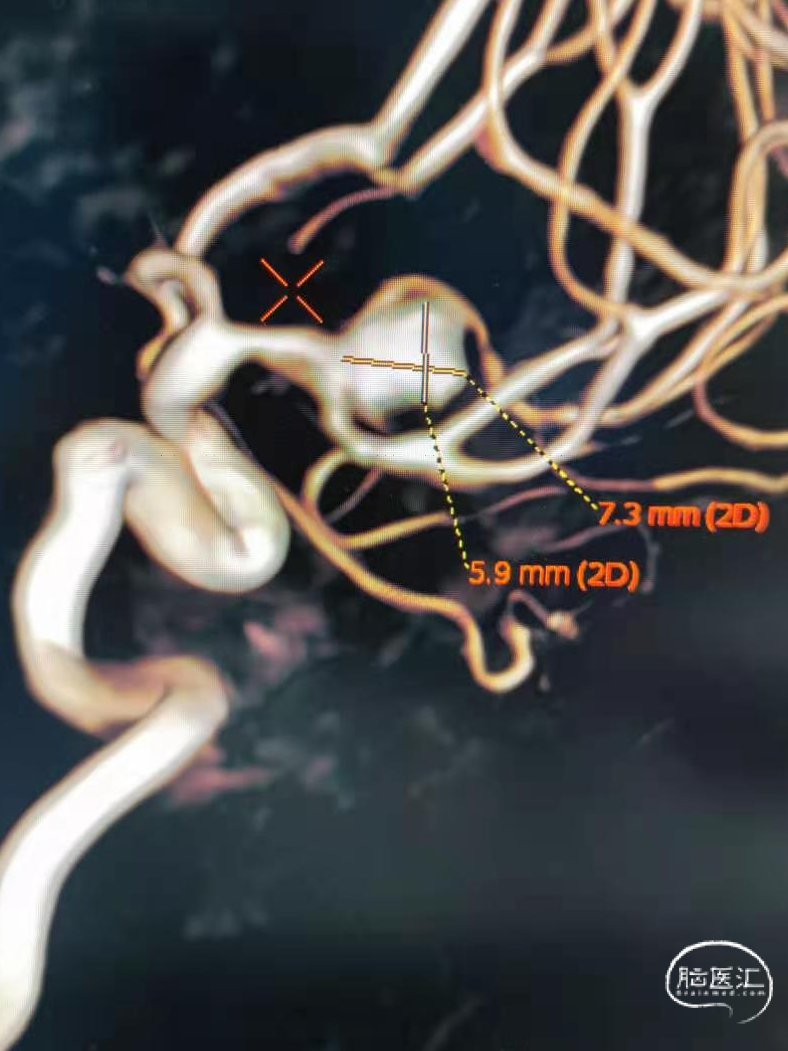

脑血管造影显示右侧大脑中动脉分叉部宽颈动脉瘤,约7.4-7.0-6mm大小。动脉瘤为不规则形态,右侧中动脉上下支干均受累,其中上支干纤细约1.0mm,自瘤体近瘤颈处发出。

术前影像